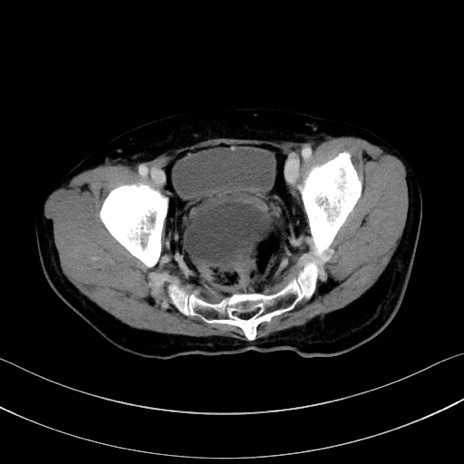

冠状断像

【症例】60歳代男性

【主訴】嘔吐

【現病歴】胃癌にて胃全摘後。食思不振が悪化し、夜中に嘔吐することがある。

【既往歴】胃癌、胃全摘、脾摘、胆摘後

【データ】WBC 5900、CRP 10.56